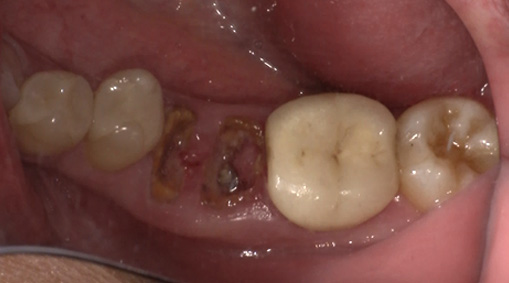

傷んだ歯を抜歯します。

親しらずを抜歯して、移植します。